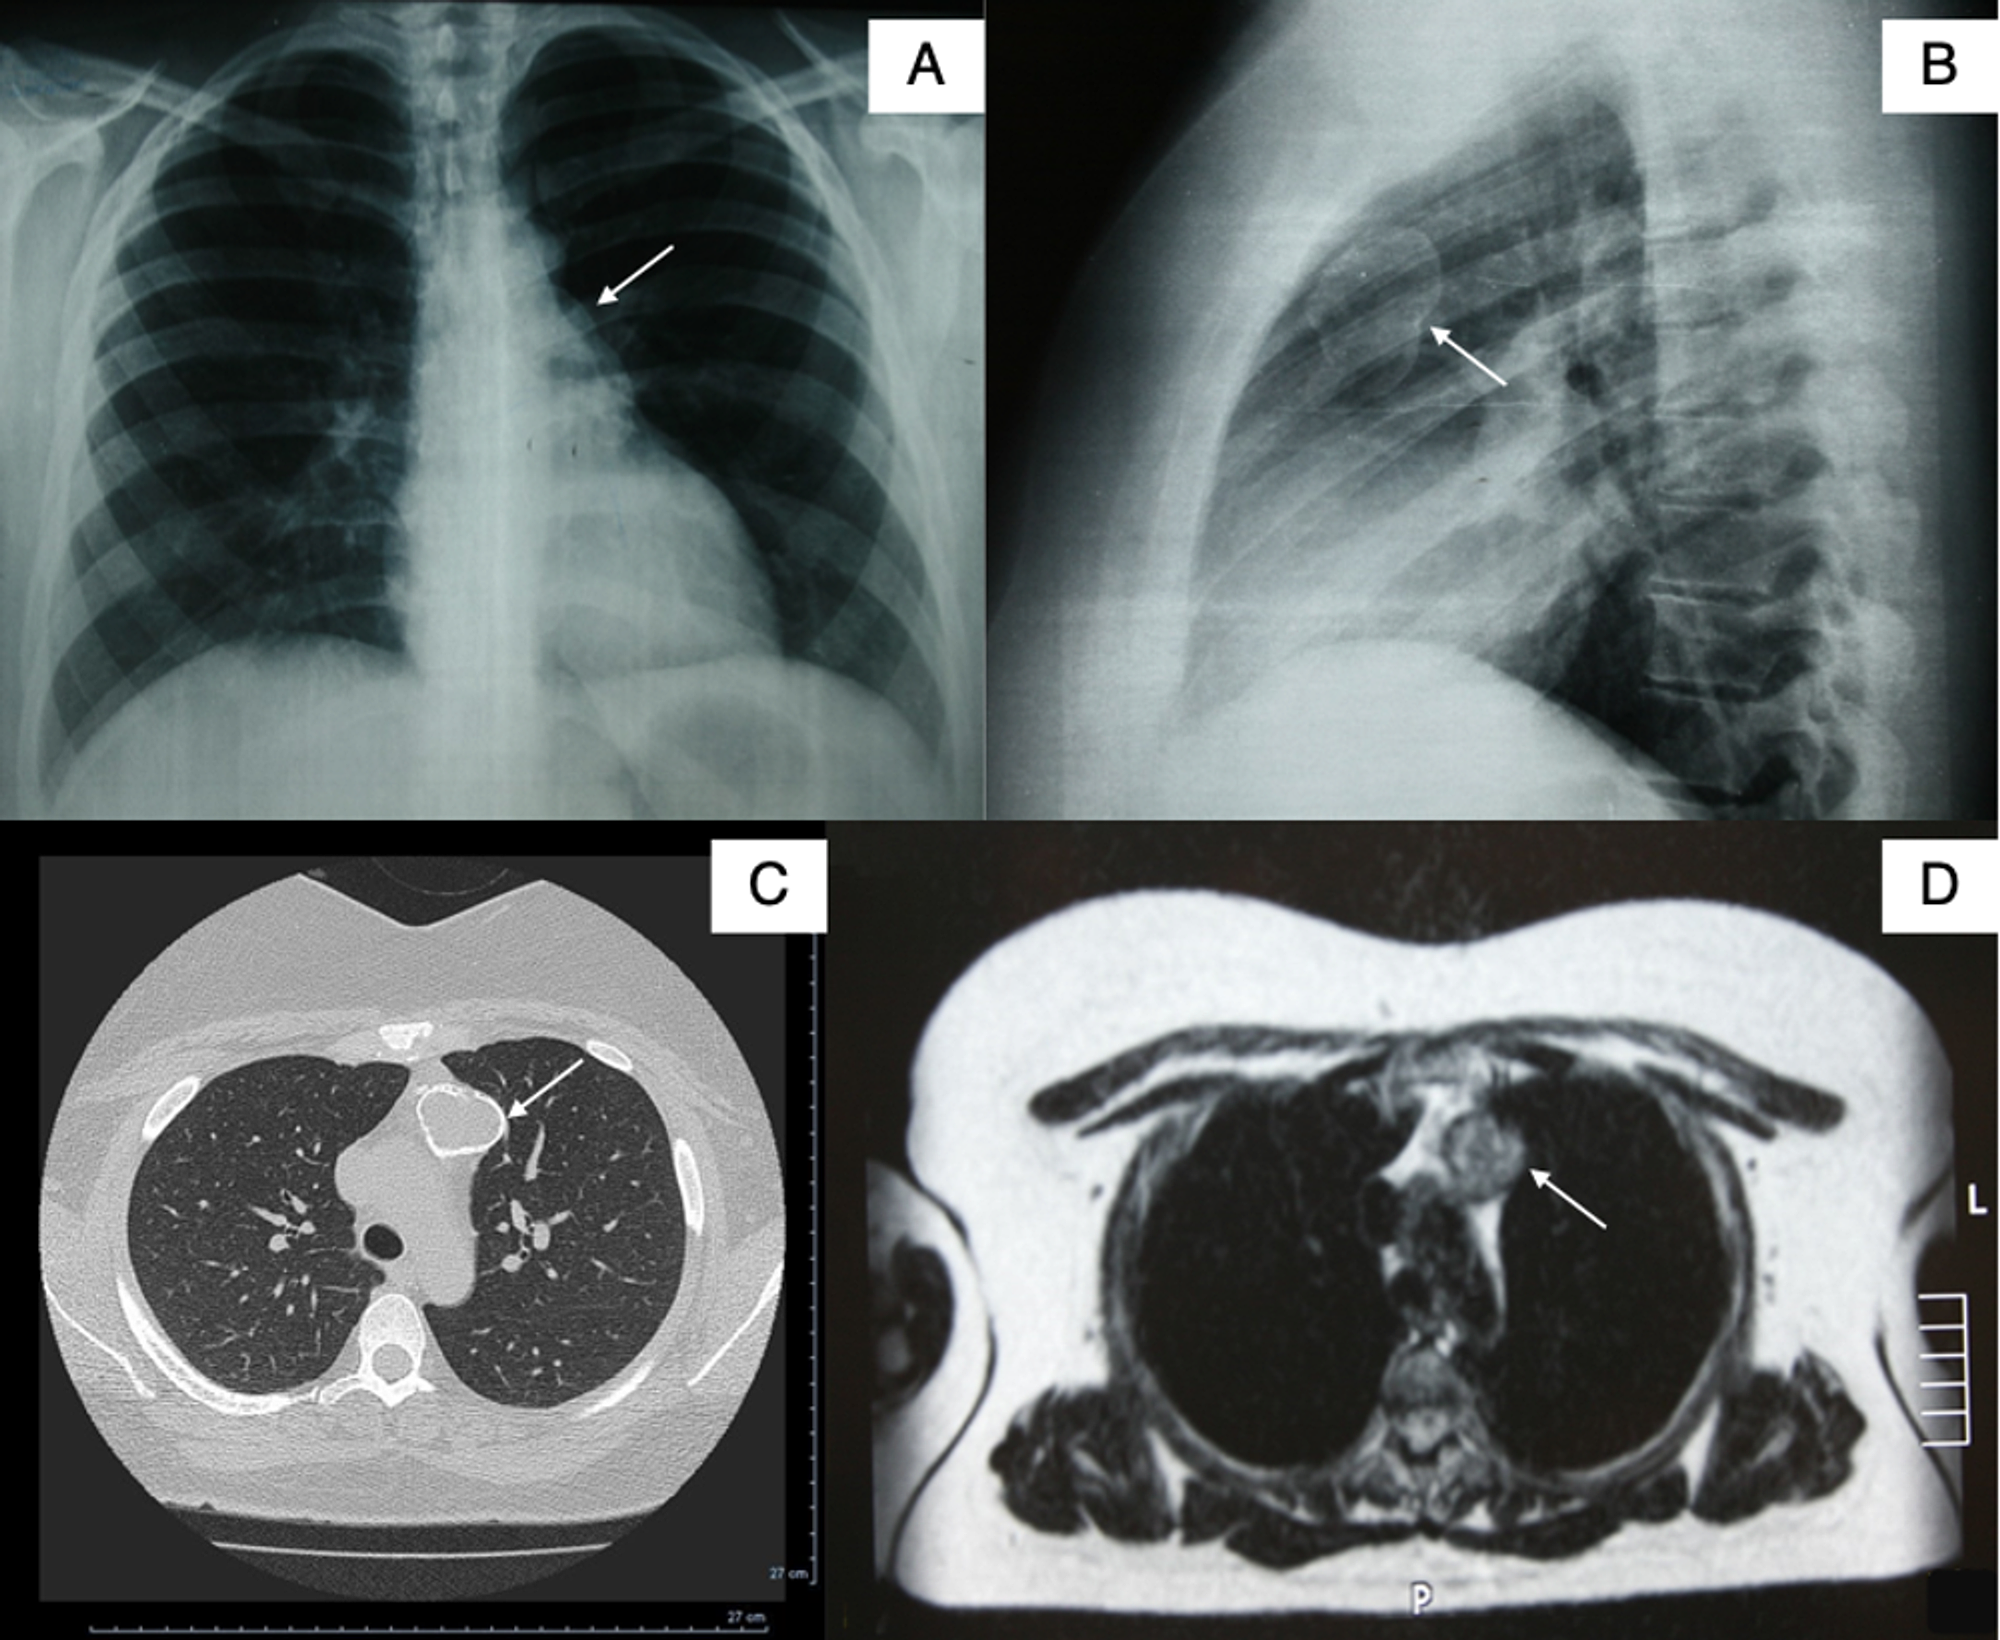

Figure 1 from Correlative Imaging in a Patient with Cystic Thymoma CT Thymic Cyst Vs Cystic Thymoma Radiology Hyperdense thymic cysts are often misinterpreted as solid on ct. Web differentiation of thymic cysts from solid lesions is more readily and consistently achieved with mri. Web the radiologic differential diagnosis for such lesions of the anterior mediastinum includes cystic teratoma, lymphangioma, hemangioma, and, as noted. Web distinguishing these masses on diagnostic imaging is fundamental to guide the proper management. Thymic Cyst Vs Cystic Thymoma Radiology.